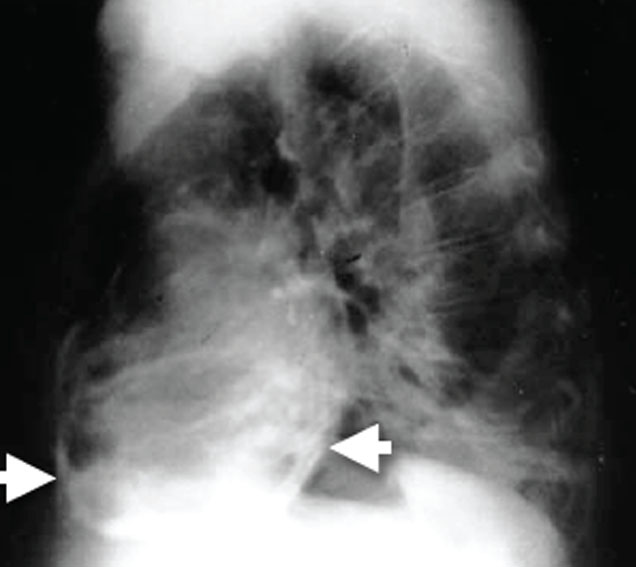

• péricardiques : formant de bandes linéaires autour de la silhouette cardiaque. Elles prédominent au niveau des sillons et de la face inférieure du coeur. Elles peuvent au maximum former une coque calcaire comprimant le coeur (figure 33).

Figure 33 : Exemple de calcifications : Calcifications péricardiques (flèches)